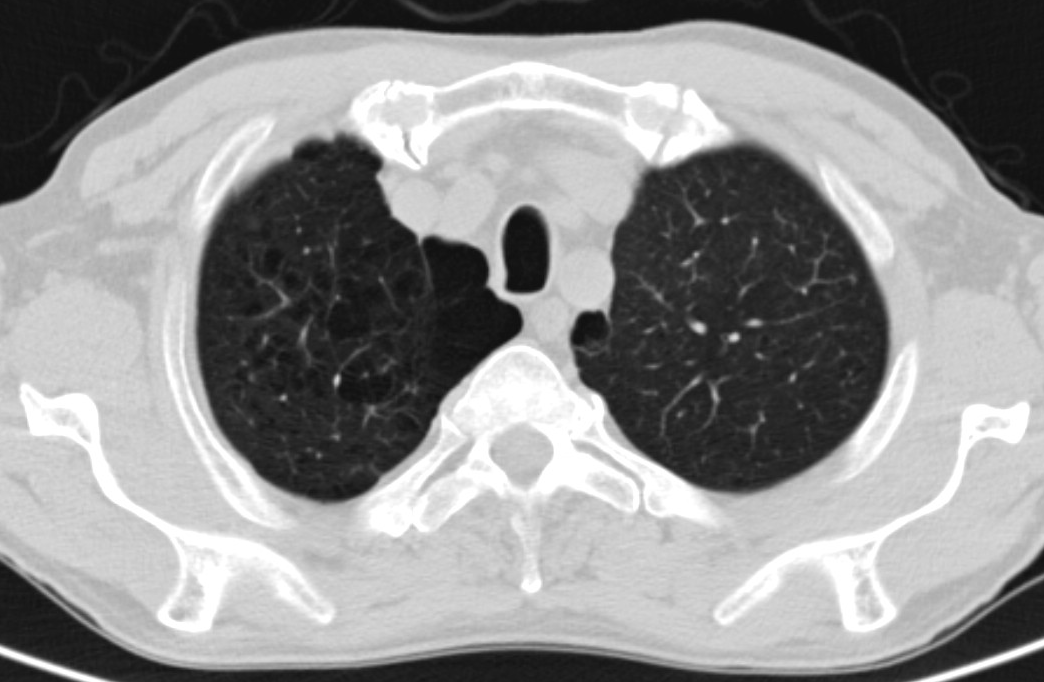

4: Miliary pattern: sarcoidosis, CT, lung window. Axial image and sagittal reformat.

A 67 year old female suffering from COPD. Bilateral rough branching interstitial widening and patchy, miliary nodules with perihilar dominance along the bronchovascular fibres and the fissures.